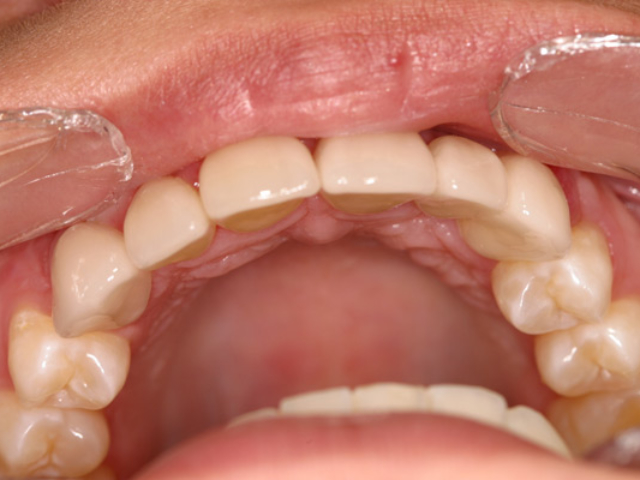

Case Study 8

Problem: This young patient was born with no lateral incisors.

Plan: Our plan… placed patient in orthodontics to straighten and gain the needed space then placed implants with crowns.

Treating genetic conditions.